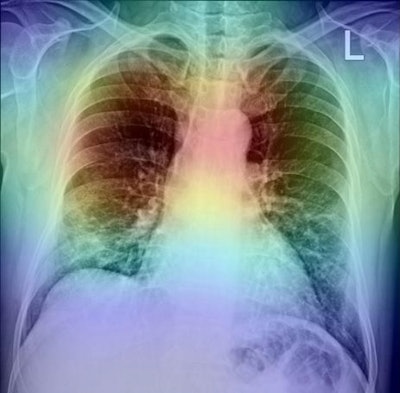

In addition, to further analyze the proposed method, the researchers used gradient-based class activation mapping (GradCAM) to represent the AI model's decision area on a heat map, which they suggested could help radiologists evaluate the chest area more accurately.

An AI model's decision area visualized on a chest x-ray heat map. Image courtesy of Radiography.The aim of the study was to detect and identify COVID-19 in patient images. While reverse transcription polymerase chain reaction (RT-PCR) tests are the most common method of COVID-19 diagnosis, they can be time-consuming, and results may have a high level of false-negatives, the authors wrote.